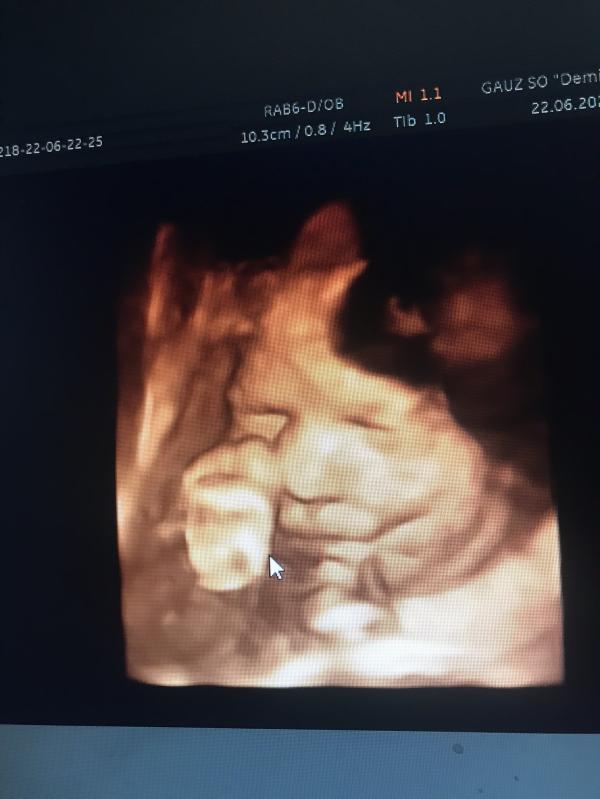

Вчера ходили с мужем на 4-д узи, божечки, это тааак волнительно 🥰

Сказали, что у нас ооочень серьёзный парень)))

Только под конец узи удостоил нас своей улыбкой😄

@silkovioletta4, Около 2-х кг) сказали немного больше нормы, но ничего страшного)) хотя у многих на этом сроке такой вес 🤷🏼♀️